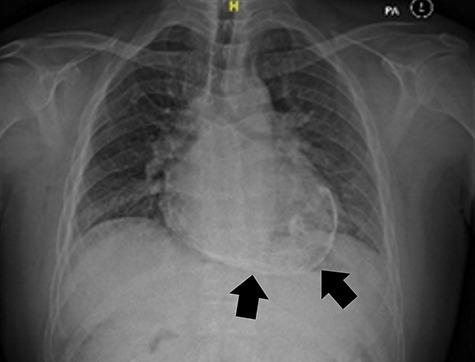

Constrictive pericarditis is a disabling disease of the heart, which causes cardiac diastolic dysfunction. We present a case of a 44-year-old gentleman with a history of blunt chest trauma who presented with constrictive pericarditis with right-sided heart failure. Imaging studies revealed a calcified pericardium. He underwent an uneventful pericardiectomy. Calcification is common yet rare if it involves the pericardium. It normally occurs following fibrosis and adhesion which are associated with the chronicity of the disease, hence creating more challenge to the operating surgeon in the pericardiectomy procedure.